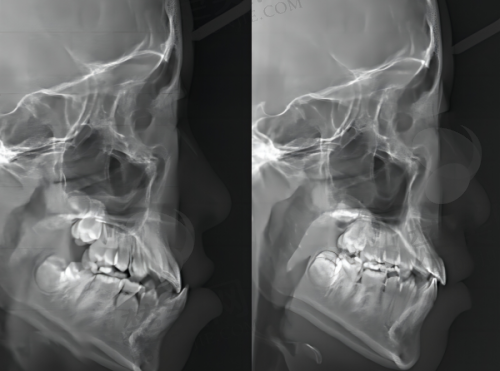

在设备方面,门诊部配备了精良的诊疗设备。这些设备能够更精细地诊断口腔问题,为治疗提供有力的支持。比如口腔CT设备,可以清晰地显示口腔内部的结构,帮助医生更正确地制定治疗计划;精良的牙齿矫正设备,能够实现更严谨的牙齿移动,缩短矫正周期。